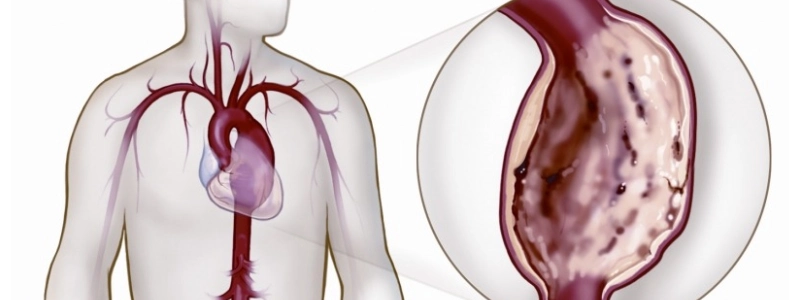

Aneurisma da aorta é uma dilatação que ocorre na parede da artéria. Embora possam se desenvolver em outras artérias, a aorta é a estrutura de maior incidência dos aneurismas.

Em se tratando dos aneurismas que acometem esta artéria, estes podem ocorrer tanto na porção abdominal, quanto na torácica. A maior ocorrência, contudo, se dá abaixo das artérias renais, ou seja, na porção abdominal.

Como se caracteriza o aneurisma da aorta torácica

Este tipo de aneurisma ocorre quando a aorta se apresenta, no porção localizada no interior da caixa torácica, com dilatação de 50% do seu diâmetro ideal. Este segmento se estende da saída do coração até o diafragma.

Veja de que forma se manifesta o aneurisma da aorta abdominal

Nesse caso, há dilatação de mais de 50% de diâmetro da porção abdominal da aorta. Tal segmento tem início no diafragma e termina na bifurcação em artérias ilíacas.

Verifica-se que este tipo de aneurisma é mais comum logo abaixo das artérias renais. Assim sendo, torna-se possível corrigir a condição por meio do emprego de endoprótese com bifurcação simples.